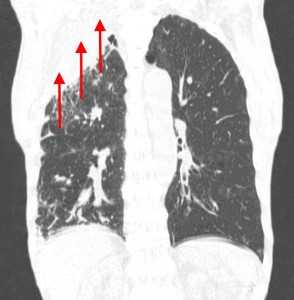

Лимфогенные метастазы на рентгене и КТ выглядят как множественные мелкие очаги с диссеминированным распространением, локализованные в междольковых перегородках, в плевральных листках. Вокруг можно видеть характерную картину ракового лимфангиита. Кроме того, практически всегда выявляются патологически измененные и увеличенные лимфатические узлы средостения. Лимфогенное метастазирование необходимо дифференцировать с милиарным туберкулезом, саркоидозом. Иногда это требует привлечения Второго мнения.

Лимфогенные метастазы проявляются увеличением лимфатических узлов средостения в сочетании с мелкоочаговой диссеминацией с очагами до 2-3 мм в диаметре вблизи плевры и в междольковых перегородках, а также по ходу бронхов и сосудистых пучков.